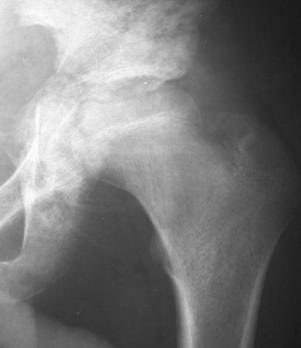

股骨头骨骺缺血性坏死:骨骺变小、碎裂变形,颈短粗,头向外移,内侧间隙增宽。

成人股骨头缺血性坏死:股骨头变形,增骨质生硬化囊变并存;左侧间隙变窄,右侧间隙正常。关节间隙变窄,退行性骨关节病,股骨头呈磨菇头状变形

好发部位:股骨头、胫骨结节、椎体骺板、腕舟月骨、足舟骨等。

病因:外伤、营养、解剖缺陷、代谢内分泌。

临床表现:局部疼痛,运动障碍。